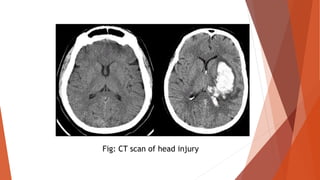

 Investigation specific for cause: Ultrasound abdomen, Doppler study in

vascular injury and often angiogram, chest X-ray in hemothorax, CT scan in

major injuries, CT head in head injuries.

Fig: CT scan of head injury

MEASUREMENT OF BLOODLOSS  Clot size of a clenched fist is 500 ml.  Blood loss in a closed tibial fracture is 500-1500 ml in a fracture femur is 500- 2000 ml.  Weighing the swab before and after use is an important method of on table assessment of blood loss.  Hb% and PCV estimation.  Blood volume estimation.  Measurement of CVP or PCWP.  Investigation specific for cause: Ultrasound abdomen, Doppler study in vascular injury and often angiogram, chest X-ray in hemothorax, CT scan in major injuries, CT head in head injuries.

Fig: CT scanof head injury